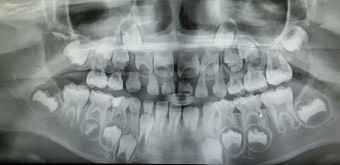

하지만 구강 내 세균인 치태(Plaque, 플라크)가 치아 표면에 쌓이면서 염증이 시작되며, 이 치태는 단단해지면 스케일링 없이는 제거가 불가능합니다.

■ 치태의 정체와 세균 번식

산소가 없는 잇몸 아래는 혐기성 세균이 주로 번식 → 잇몸 깊은 염증의 주범

■ 충치(치아우식증)의 주 원인균

- 뮤탄스균(S. mutans, S. sobrinus)

- 당분을 분해해 산을 생성, 치아를 탈회시킴

- 젖산 생성 → pH 감소 → 충치 부위는 뮤탄스균 위주로 세균 재편

■ 치주염의 주요 원인균

- 만성 치주염:

- Porphyromonas gingivalis

- 급성 치주염:

- Aggregatibacter actinomycetemcomitans

- T. denticola

- 기타:

- Prevotella, Fusobacteria, Candida albicans, Tannerella, Streptococcus oralis 등